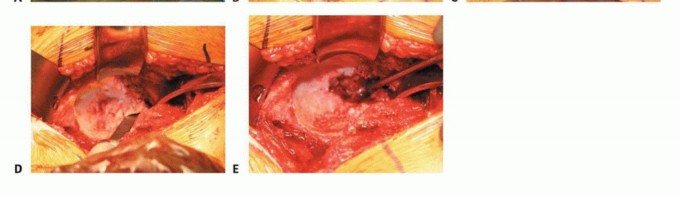

الشكل 1:

صورة بالأشعة السينية للورك تظهر تغيرات تنكسية متقدمة مثل النتوءات العظمية وانسداد مساحة المفصل.